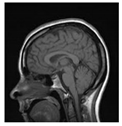

Table 1.

Results of marking and encrypting a medical image.

Table 1 shows the original image, marked image, encrypted image, the decrypted image, and the correlation between extracted blocks and original blocks after decryption using the Double Random Phase Encryption. It is clear that the encryption increases the security, and the mean correlation between the recovered mark and the original mark is measured to be 0.9 in both cases.

The PSNR and SSIM between the original image and marked image are 35.99 db and 0.97, respectively, which means that the marking does not affect the quality of the original image and keeps the invisibility of mark in the image. After encrypting the marked image using the DPRE algorithm, the results show that PSNR and SSIM between the encrypted and marked image are 12 db and 0.1, which verifies the strength of the suggested cryptosystem, as there is no similarity between them. Moreover, the results show that the correlation between the embedded rows and columns with the original is near to 1, verifying the robustness of the mark or signature.